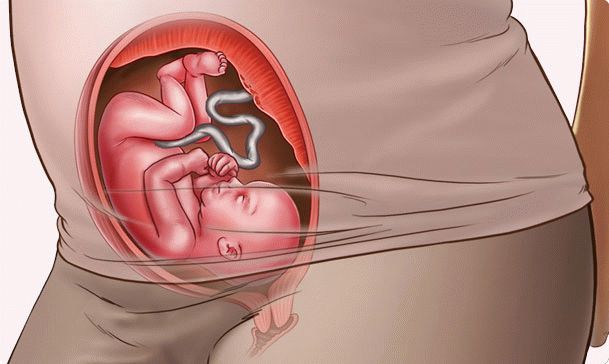

Voici à quoi ressemble le fœtus à 24 semaines:

Toujours en cours:

- minéralisation osseuse;

- la formation de gyrus cérébral;

- mouvements réflexes (déglutition, respiration, mouvements);

- un cœur développé compte environ 140-160 battements par minute.

Les proportions du corps fœtal sont près de 100% proches des paramètres du nouveau-né. La seule différence est que le bébé a l'air mince, avec des bras et des jambes très fins et une peau ridée. En effet, la couche de graisse sous-cutanée n'est pas complètement formée.